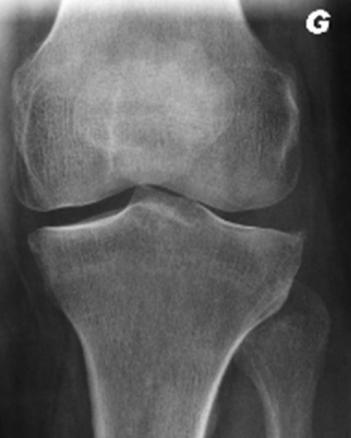

Ostéophytose du genou gauche

Gonalgie gauche interne avec ostéophytose sans pincement du compartiment fémoro-tibial interne.